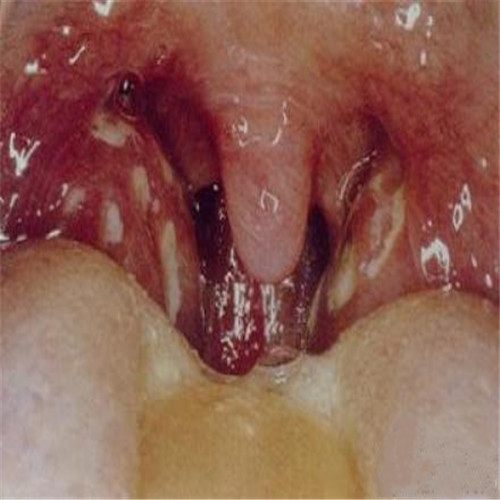

呼吸道感染兩側發炎